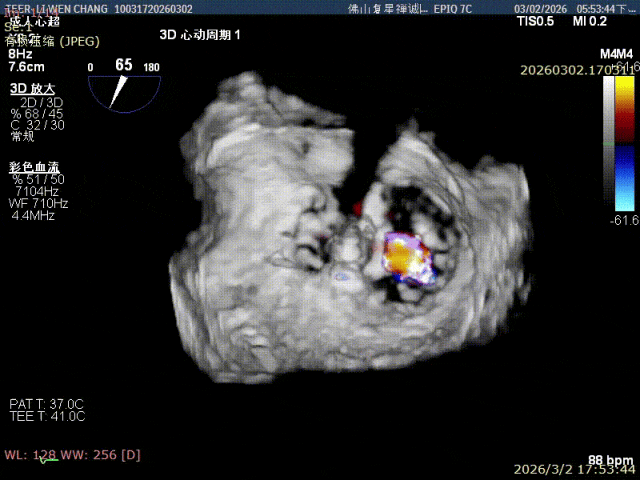

手术过程

释放XW0612瓣膜夹

组织桥稳定

夹子内外侧均有微量反流, 且一区还存在脱垂